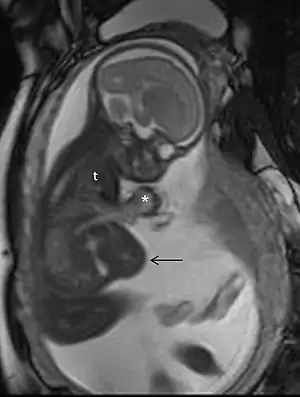

MRI of a fetus with Pentalogy of Cantrell.

Magnetic resonance imaging (MRI), without MRI contrast agents, is not associated with any risk for the mother or the fetus, and together with medical ultrasonography, it is the technique of choice for medical imaging in pregnancy.[1]